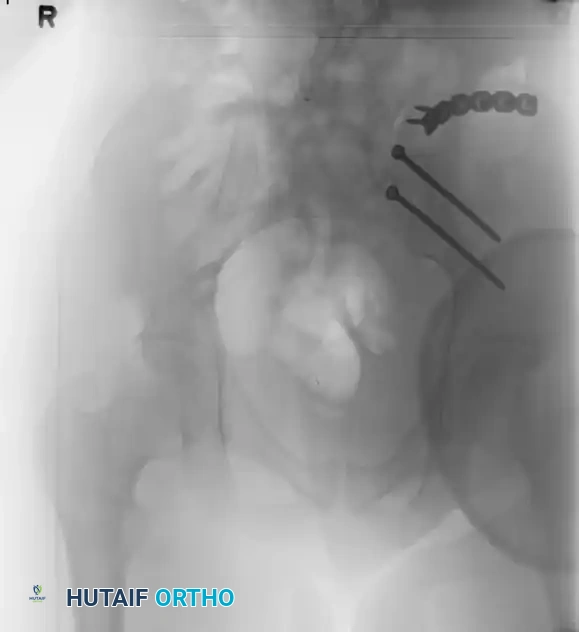

Case 3: Young-Burgess Anteroposterior Compression Type III (AP III)

An AP III injury is a completely unstable pelvic ring disruption. It involves complete disruption of the symphysis pubis (or anterior rami) and complete disruption of both the anterior and posterior sacroiliac ligamentous complexes. The hemipelvis is both rotationally and vertically unstable.

Preoperative Evaluation:

The preoperative AP, inlet, and outlet views demonstrate severe pubic diastasis, bilateral pubic rami fractures, and gross widening/displacement of the posterior SI joints.

FIGURE 56-45: Young and Burgess anteroposterior type III (AP III) pelvic ring injury with pubic diastasis and bilateral pubic rami fractures. A-C, Preoperative anteroposterior, inlet, and outlet views, respectively. D, Preoperative CT scan.